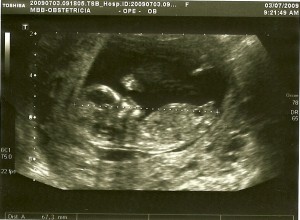

Hoje foi  a primeira oportunidade do Fernando me acompanhar à consulta.

Primeiro fizemos a ecografia e depois fomos à consulta com o obstetra e a enfermeira e depois fui fazer o rastreio bioquímico, uma análise de sangue que permite juntamente com outros exames de diagnóstico pré-natal calcular o risco da ocorrência de algumas patologias. A patologia mais divulgada de entre as possíveis de despistar é o Sindrome de Down (trissomia 21), que é a mais conhecida pela sua frequência e relevância em termos sociais.

Foi emocionante ver o nosso pequeno feto com 12 semanas e 5 dias a flectir e esticar as pernas, a mexer a mão e a abrir e fechar a boca! Conseguimos contar os dedos das mãos, ver os rins e a bexiga, ver e ouvir o coração a bater, enfim…

É um momento em que nos apercebemos que é real, existe mesmo um pequeno ser dentro de mim! E que tem de ser protegido porque é muito frágil!

As imagens do nosso bebé a movimentar-se dentro do meu útero é uma imagem que não me sai da cabeça e da do Fernando! Lindo! Ainda bem que temos toda esta tecnologia à nossa disposição!

O vínculo entre a tríade (mãe/pai/filho) já está em formação!

eco12s+5d

2eco12s5d